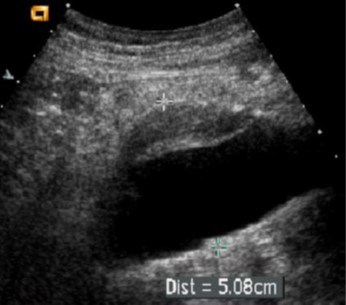

Διάγνωση και παρακολούθηση με υπέρηχο

Το μέγεθος της αορτής απεικονίζεται με τη βοήθεια υπερήχου.

Ανάλογα με το μέγεθος προτείνεται αρχικά παρακολούθηση και επανέλεγχος με υπέρηχο σε τακτικά χρονικά διαστήματα ή αν το μέγεθος πλησιάσει το ανώτατο όριο τότε το επόμενο βήμα είναι η αξονική τομογραφία και ενδεχομένως το χειρουργείο